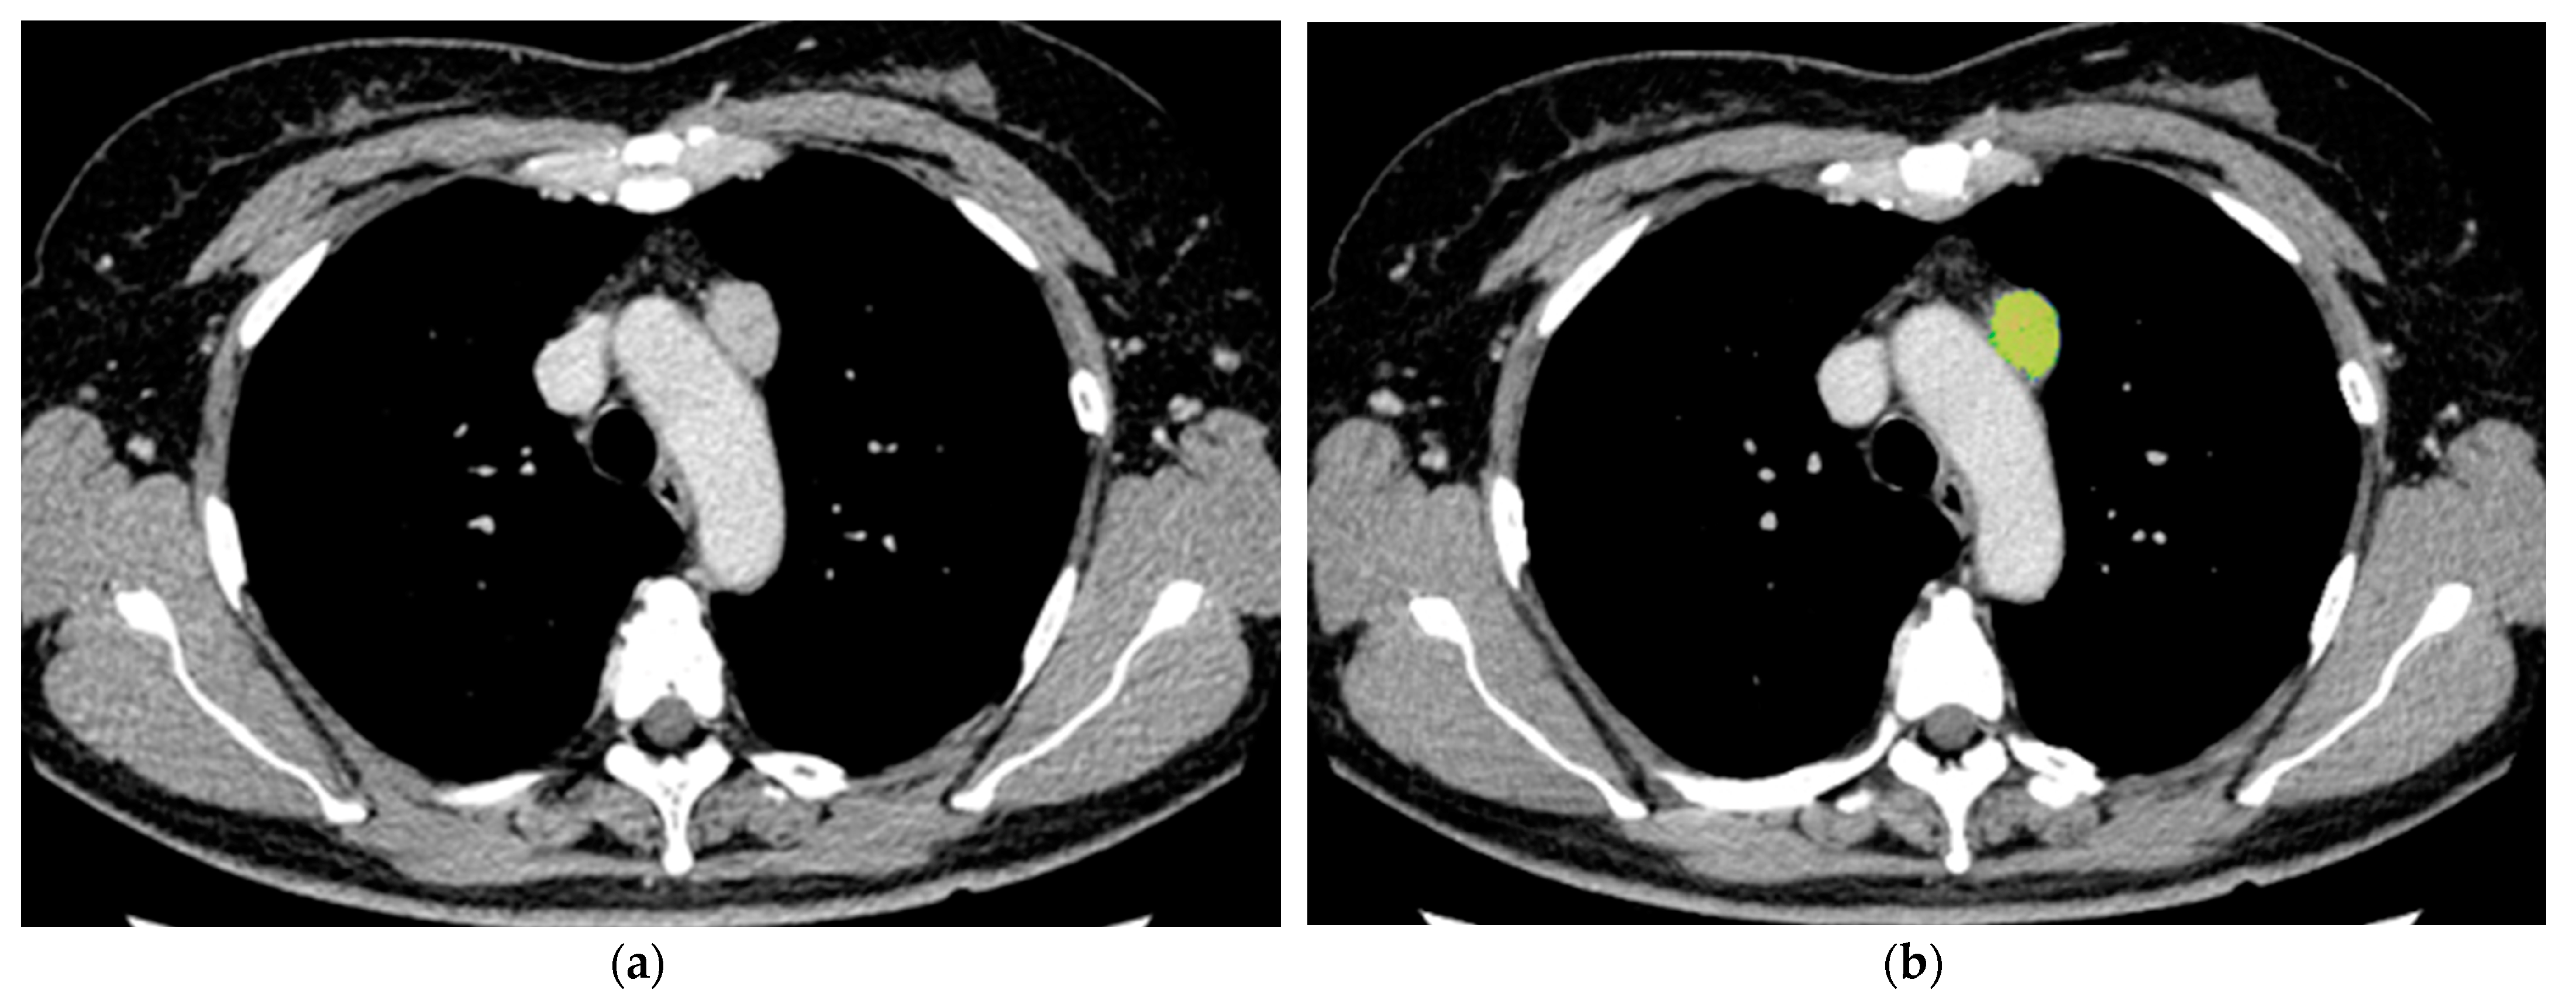

2.3. Image Analysis

2.4. Histological Evaluation